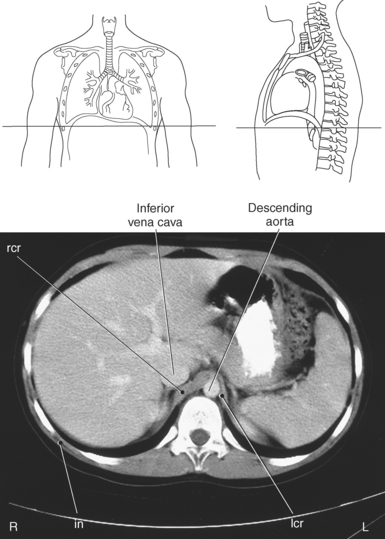

Muscles associated with respiration are the intercostal, serratus posterior superior, serratus posterior inferior, and the diaphragm (Table 6.3). The spaces between the ribs, or the intercostal spaces, are filled with three layers of intercostal muscles (external, internal, and innermost layer) (Figures 6.106 through 6.108). These muscles act together to elevate the ribs and expand the thoracic cavity, as well as keep the intercostal spaces somewhat rigid. The serratus posterior superior muscle spans from C7-T2 to ribs 2 to 5 and acts to assist forced inspiration, whereas the serratus posterior inferior muscle spans from T11-L2 to ribs 9 to 12 and acts to assist forced expiration (Figures 6.109 through 6.110). The diaphragm is a large dome-shaped muscle that spans the entire thoracic outlet and separates the thoracic cavity from the abdominal cavity (Figure 6.111). It is the chief muscle of inspiration because it enlarges the thoracic cavity vertically as the domes move inferiorly and flatten. The muscle fibers of the diaphragm converge to be inserted into a central tendon, which is situated near the center of the diaphragm immediately below the pericardium, with which it is partially blended. The diaphragm is attached to the lumbar spine via two tendinous structures termed crura (Figures 6.111 through 6.113). The right crus arises from the anterior surfaces of L1-L3, whereas the left crus arises from the corresponding parts of L1-L2 only. The left and right crura join together across the ventral aspect of the abdominal aorta to form the medial arcuate ligament. Three major openings, or hiatuses, of the diaphragm allow for the passage of vessels and organs from the thorax to the abdomen. The aortic hiatus allows for the passage of the descending aorta, azygos vein, and thoracic duct. The caval hiatus allows for the passage of the inferior vena cava and the right phrenic nerve. The esophageal hiatus allows for the passage of the esophagus and the vagus nerve.

Figure 6.112 Axial, T1-weighted MR scan of abdomen with crura.

Key: rcr, Right crus; IVC, inferior vena cava; da, descending aorta; lcr, left crus.

Figure 6.113 Axial CT scan of chest with crura.

Key: rcr, Right crus; lcr, left crus; in, intercostals.